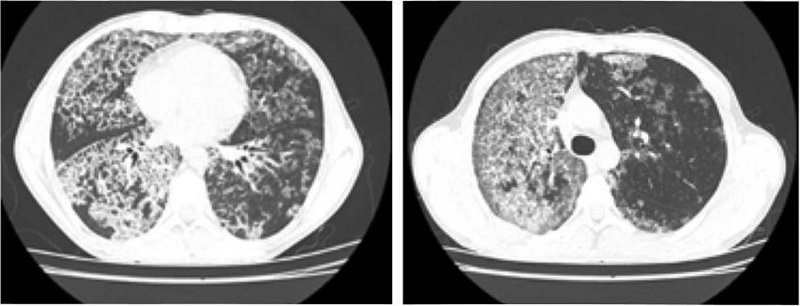

Los hallazgos imagenológicos son sugestivos, pero no son diagnósticos por sí solos: en la radiografía de tórax es característico encontrar opacidades alveolares bilaterales de distribución perihiliar sin broncograma aéreo o “patrón en alas de murciélago”; por otro lado, en la tomografía computarizada (TAC) se espera encontrar el signo del “empedrado” que consiste en un engrosamiento interlobulillar asociado a opacidades difusas en vidrio esmerilado 9,11.

Al ingreso se solicita hemograma con leucocitos: 6300 x 103 mm3, #neutrófilos: 4020, #linfocitos: 1600, hemoglobina: 17,9 g/dl, hematocrito: 53,2 %, plaquetas: 315.000 mm3, radiografía de tórax con evidencia de zonas en vidrio esmerilado generalizadas con predominio en hemitórax derecho (figura 1) por lo cual se solicita tac que evidencia múltiples áreas parcheadas de distribución generalizada de mayor compromiso apical derecho en relación con áreas de vidrio esmerilado asociado a engrosamiento del intersticio interlobulillar que genera patrón en “empedrado” (figura 2).